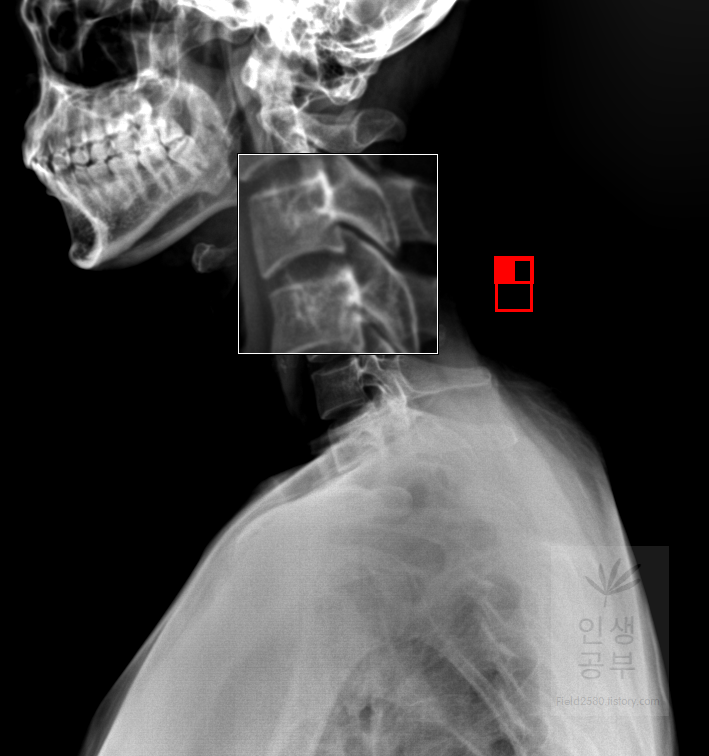

돋보기 화면에 ±가 있는 버튼을 이용해서 화면 전체의 크기를 조절할 수 있는 반면에 부분적인 부분만 확대할 수 있는 방법이 있습니다. 바로 매직 글래스메뉴를 이용해서 부분적인 확대 버튼을 이용하실 수 있습니다. 또한 부분적인 확대 화면 안에서도 추가적인 확대와 축소를 이용할 수 있습니다.

부분적으로 확대해서 보고 싶은 X-ray화면에 마우스 왼쪽을 클릭해서 확대해줍니다. 부분적으로 네모칸이 생기면서 선택한 부분을 조금더 크게 보여주는 창이 생깁니다.

만약에 조금 더 크게 보고 싶다면 마우스 왼쪽을 누른 상태에서 Ctrl을 누른 후에 11시 방향이나 12시 혹은 1시 방향으로 올려주면 매직 글래스 화면 내에 부분적으로 확대된 X-ray 화면이 더 커집니다.

다시 축소하고 싶다면 마우스 왼쪽을 누른 상태에서 Ctrl을 누른 후에 4시 6시 혹은 8시 방향으로 내려주면 매직 글래스 안에서 부분적으로 확대된 X-ray 화면을 줄일 수 있습니다.